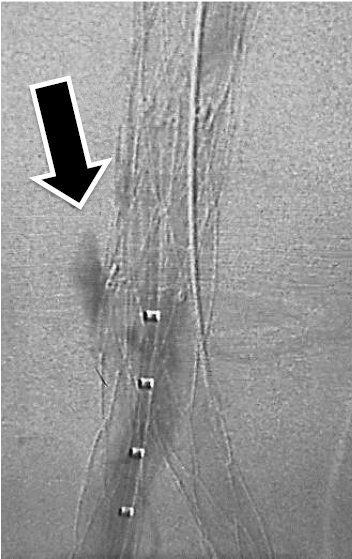

Qual o tipo de endoleak se observa na imagem abaixo?